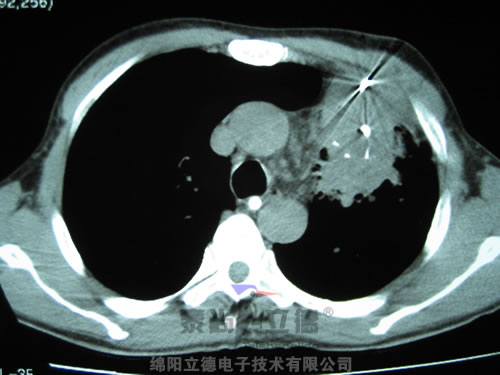

2.jpg

晚期肺癌RF治療后3個月